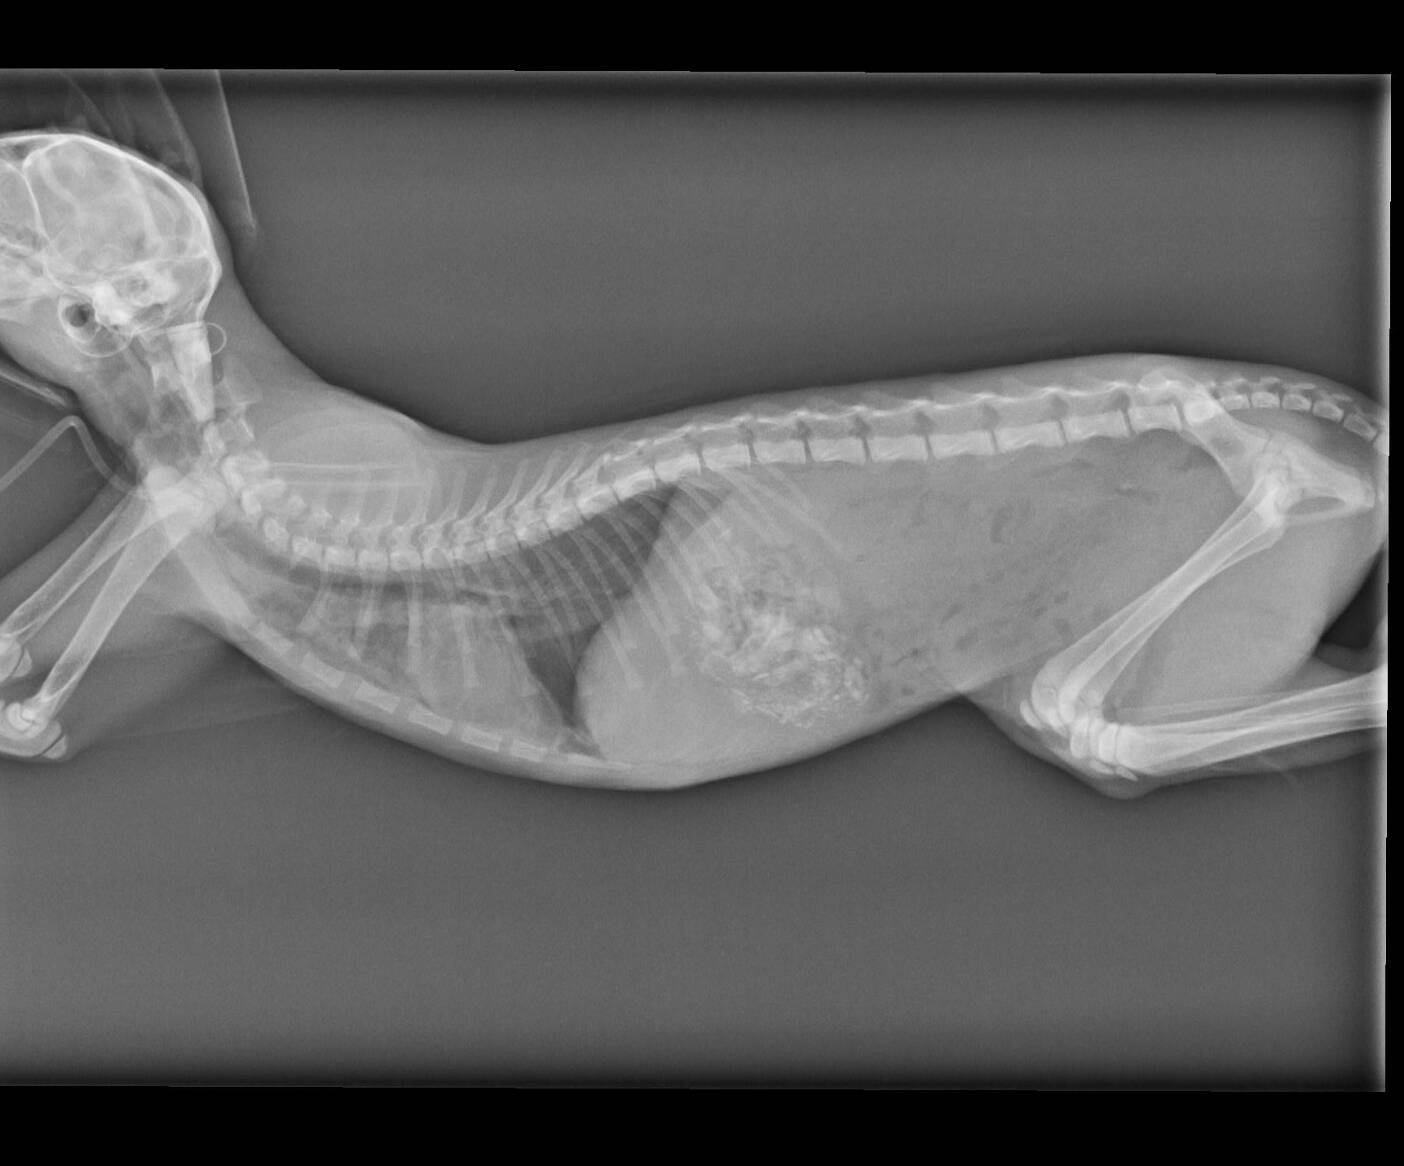

主題: 被車撞到的小貓平安 申請者姓名: 梁仕宏 花色: 申請日期: 2020-05-15 15:12:04 申請者部落格: 申請者臉書網址: 梁仕宏 所在縣市/合作醫院: 高雄市/小新動物醫院 治療費用: 5000元 需求人數: 22人 已結案 (2024-05-31 18:16:25) 報名人員: philtery x10(已付款)、艾曼達、艾曼達 x7、艾曼達 x4(已付款)、粉圓(已付款)、派派 x5(已付款)、superwu、superwu(已付款)、Candice(已付款)、 候補人員: 動物病情說明: 安安是隻約三個月大的小賓士,可能是年紀太小不會過馬路,又或是因騎士沒注意而撞到牠,牠被撞後緊張逃進路邊診所,好心的工作人員洽好是社團貓友因而在社團求援,由於案發地在我家附近,通報時間又是4月13日晚上近9點,時間非常緊迫,怕醫院近關門時間,所以我立刻到現場救援並聯絡醫院等我將牠送醫。 動物近況說明: 安安在醫院積極幫忙治療下,經過兩三天已脫離險境,身體狀況也好轉,但醫院再次觀察她,卻發現可能因為車禍關係產生赫尼亞現象,建議第一階段住院完成後休養2-3週再進行腹腔修補手術。在她住院期滿先行出院安置期間,她變的非常可愛親人,中途點也幫她洗澡整理,也積極幫她找家。非常值得慶幸的是,有好心的家庭願意認養,而且她的赫尼亞現象也持續改善,所以再帶她回醫院複診,確認修補手術可合併日後結紮一起進行。感謝協會,醫院,大家的幫忙,讓她度過被撞可能失去生命的難關,找到她未來的幸福。